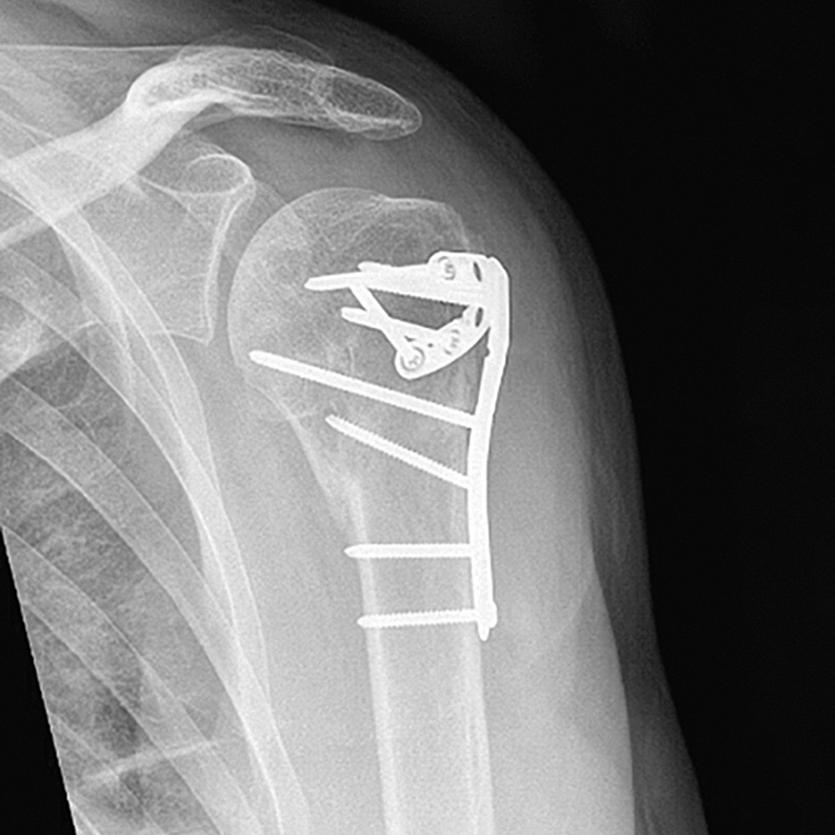

CLINICAL CASES: TAMINA CASE 5

We present a complex case of a four-part proximal humerus head-split fracture. The fracture was treated with the Bonebridge TAMINA TF 3.5mm Proximal Humerus Plate.